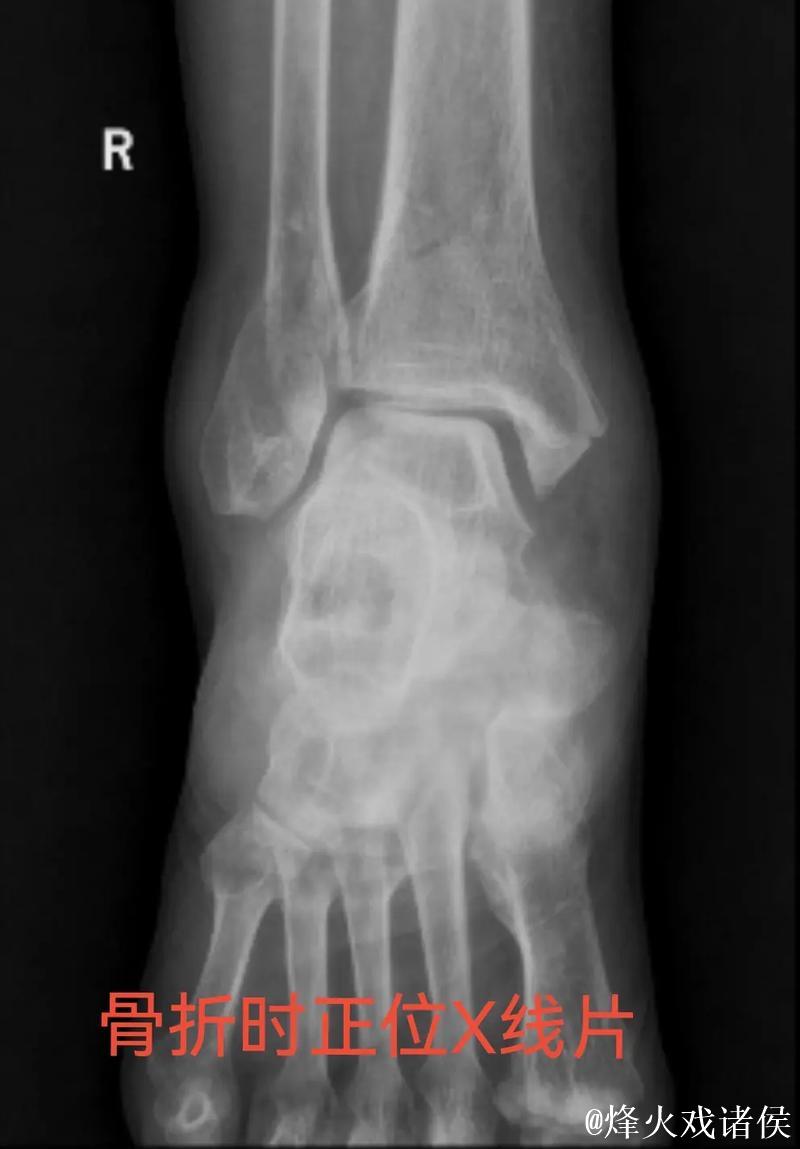

伤情解析 右踝三角韧带与腓骨骨折意味着什么

很多人在看到“右踝三角韧带断裂 右侧腓骨骨折”这样的医学表述时,只会感觉到“很严重”三个字,却未必真正理解其中的含义。踝关节三角韧带位于脚踝内侧,是一个由多条韧带组成的“组合体”,主要负责保持踝关节的内外稳定,防止小腿和足部出现异常翻转。当运动员在高速突破、急停、变向或落地时,如果脚踝遭遇过度外翻或扭转,三角韧带就可能被强行拉伸甚至撕裂。完全断裂不仅会造成剧烈疼痛,还会直接破坏踝关节的稳定性,使人几乎无法正常负重行走。与之同时出现的右侧腓骨骨折,大多与剧烈外力撞击或扭转应力有关。腓骨虽然不像胫骨那样承担大部分体重,但在踝关节的力学链条中起到重要支撑和协同作用。当韧带与骨骼在一次意外中同时受损,就意味着踝关节遭遇了极端应力,恢复与康复的难度成倍增加。

对于三角韧带断裂与腓骨骨折这种组合伤情,医学团队通常会综合评估踝关节稳定性、骨折位置与移位程度、软组织损伤范围,来决定是否采用手术治疗。若存在明显关节不稳或骨折移位,往往需要通过钢板、螺钉或钉棒内固定来重建骨性与韧带结构。在此之后,便是漫长而细致的康复周期。一般而言,骨折在数周内可以初步愈合,但韧带修复与功能恢复远比“骨头长好”更复杂。康复过程需要一套循序渐进的计划:早期的消肿与被动活动、中期的肌力与本体感觉训练、后期的专项运动模拟。每一个阶段若处理不当,都可能导致关节僵硬、力量不足或反复崴脚等后遗症。对职业运动员来说,问题不仅是“能不能走路”,而是“能不能继续高强度比赛、能不能保持原有水平”。任何轻微的落差,都可能在激烈竞争的职业舞台上被放大。